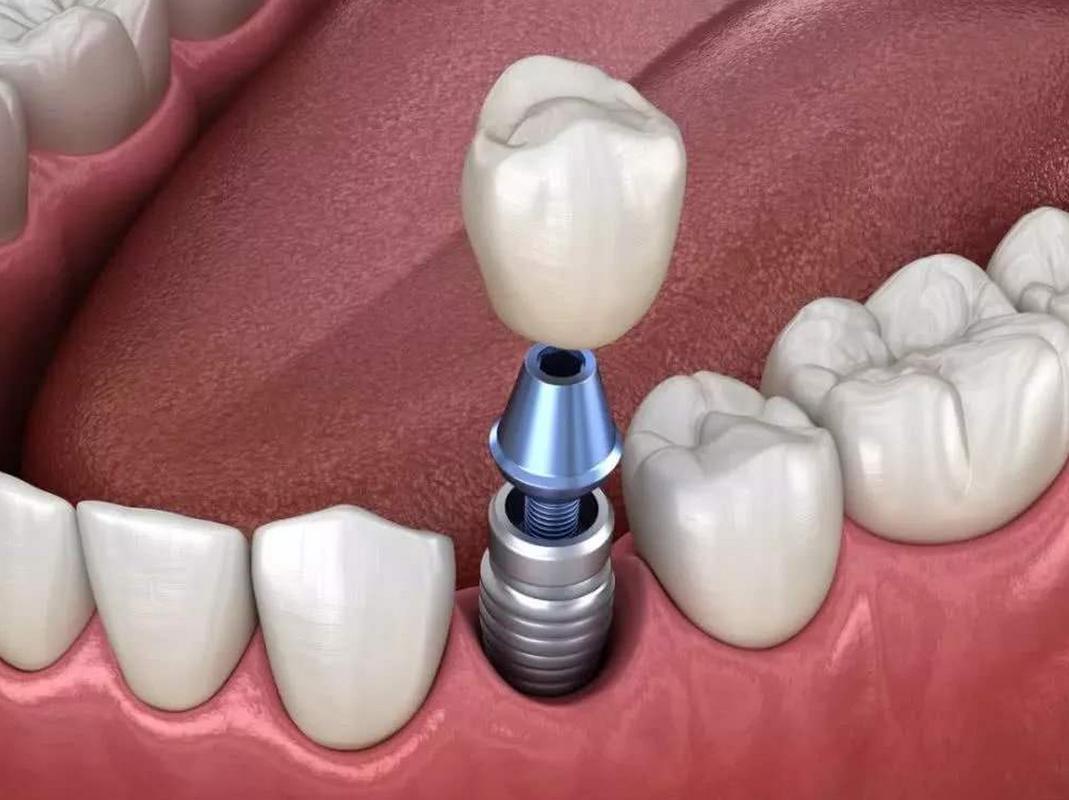

植牙的本质是将人工种植体(类似人工牙根)植入牙槽骨内,最终支撑起牙冠恢复咀嚼功能,这一过程要求种植体必须精准放置在骨量充足、避开重要解剖结构的位置,否则可能导致种植失败、神经损伤、感染等严重后果,而CT检查通过三维成像,能够为医生提供以下关键信息:

评估牙槽骨的“质量与数量”

牙槽骨的骨高度、宽度、密度是决定能否植牙及选择何种种植体的核心指标,传统X光片(如根尖片、曲面断层片)是二维影像,存在放大失真、重叠干扰等问题,无法准确测量骨量,下颌骨后区的牙槽骨可能因吸收呈现“倒凹”形态,二维片容易误判骨量充足,实际三维CT才能清晰显示骨缺损区域,避免种植体穿出骨壁。

制定个性化手术方案,提升成功率

通过CT三维重建,医生可在术前模拟种植体植入的路径、角度、深度,选择最适合的种植体型号(如短种植体、窄直径种植体),对于骨量严重不足的患者,CT能明确植骨的范围和量(如自体骨、骨粉填充量),避免术中临时调整方案,数据显示,术前CT引导的植牙手术,成功率比单纯依靠经验提升15%-20%,尤其适用于全口种植、即刻种植等复杂病例。